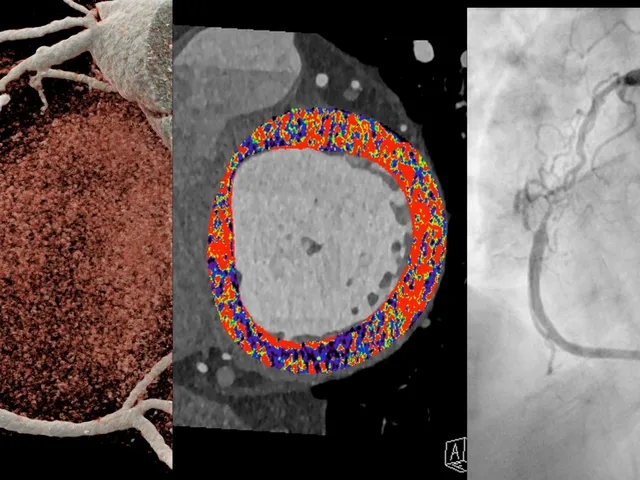

This comprehensive online mini-fellowship is designed for radiologists, cardiologists, and imaging professionals eager to understand the basics of morphological and spectral cardiac photon counting computed tomography (PCCT). The course will introduce participants to the latest advancements in cardiac imaging using photon-counting technology, which promises enhanced spatial resolution, material decomposition, and reduced radiation exposure.

The program begins with an introduction to the fundamentals of photon counting detectors, explaining how they differ from conventional energy-integrating detectors and their benefits for cardiac imaging. Participants will explore the morphological aspects of cardiac PCCT, focusing on accurate visualization of cardiac structures such as the coronary arteries, myocardium, and heart valves.

The second part of the fellowship will cover the spectral capabilities of PCCT. Learners will understand how multi-energy imaging can improve tissue characterization, plaque analysis, and differentiation of materials like calcium and contrast agents. Practical case studies will allow attendees to apply theoretical knowledge to real-world scenarios.

• Describe the morphological applications of PCCT in cardiac imaging, including detailed visualization of the coronary arteries, myocardium, and heart valves.

• Interpret spectral imaging techniques in PCCT and how multi-energy data can be used for improved tissue characterization and material differentiation (e.g., calcium, fat, contrast agents).

• Recognize the potential clinical applications of PCCT in coronary artery disease, plaque composition analysis, and myocardial perfusion imaging.